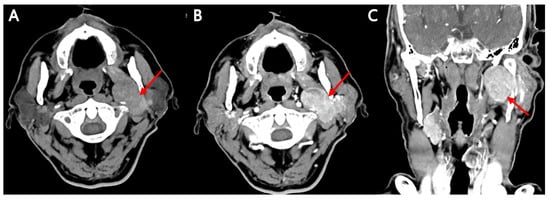

Background: The purpose of this study was to examine the relationship between qualitative characteristics and quantitative parameters from contrast-enhanced ultrasound (CEUS) and microvessel density (MVD) in hepatoblastoma (HB), as well as to investi...